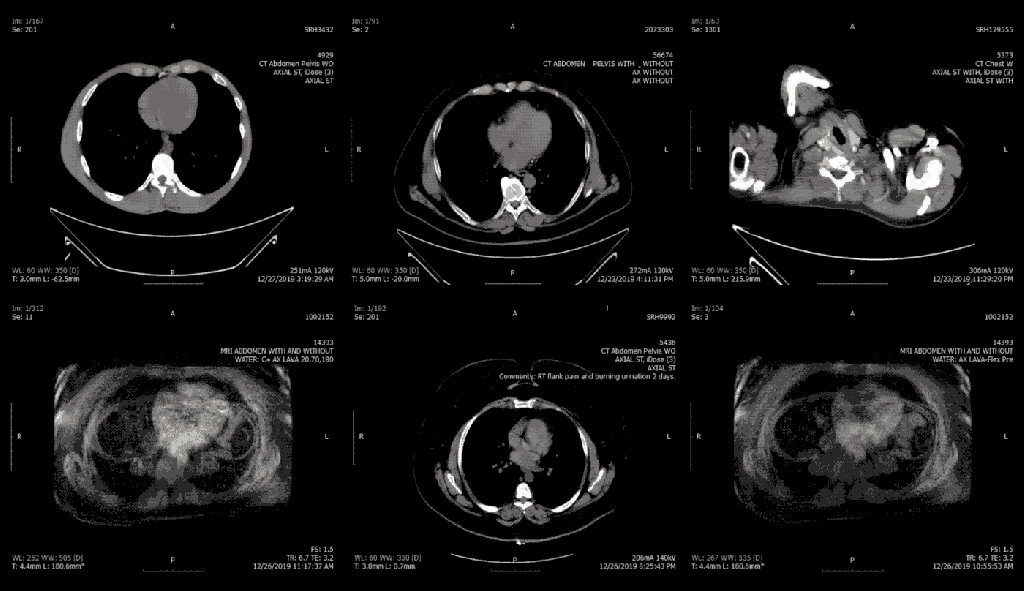

About half of all the exposed images, which include X-rays, ultrasounds and CT scans, belong to patients in the United States.

A decades-old file format and industry standard known as DICOM was designed to make it easier for medical practitioners to store medical images in a single file and share them with other medical practices. DICOM images can be viewed using any of the free-to-use apps, as would any radiologist. DICOM images are typically stored in a picture archiving and communications system, known as a PACS server, allowing for easy storage and sharing. But many doctors’ offices disregard security best practices and connect their PACS server directly to the internet without a password.

These unprotected servers not only expose medical imaging but also patient personal health information. Many patient scans include cover sheets baked into the DICOM file, including the patient’s name, date of birth and sensitive information about their diagnoses. In some cases, hospitals use a patient’s Social Security number to identify patients in these systems.

As part of our investigation, we found a number of U.S. imaging centers storing decades of patient scans.

One patient, whose information was exposed following a visit to an emergency room in Florida last year, described her exposed medical data as “scary” and “uncomfortable.” Another with a chronic illness had regular scans at a hospital in California over a period of 30 years. And one unprotected server at one of the largest military hospitals in the United States exposed the names of military personnel and medical images.

But even in cases of patients with only one or a handful of medical images, the exposed data can be used to infer a picture of a person’s health, including illnesses and injuries.